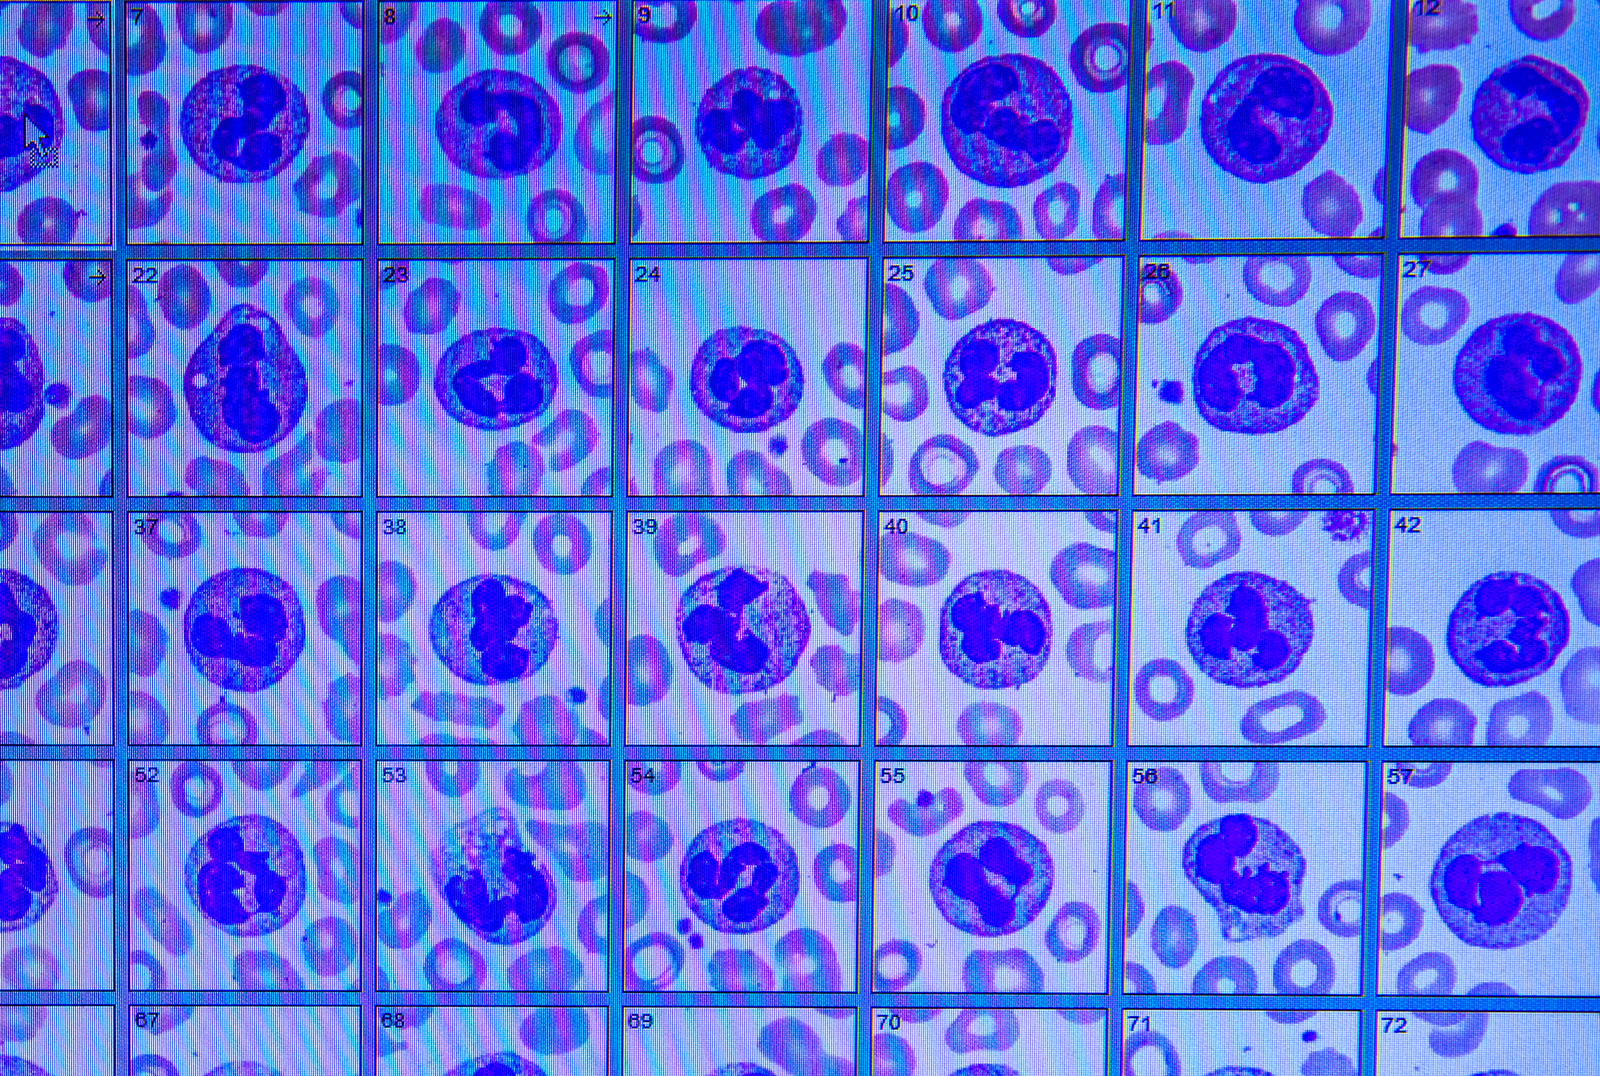

Dr. Thamboo and his team are working with the BC Cancer Agency to identify blood markers for nasopharyngeal cancer that could detect NPC in its earliest stages.

Read more about NPC and how we’re pioneering new, minimally invasive treatments for NPC and other cancers that disproportionately affect Asian Canadians.